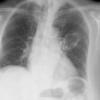

Abscess PA